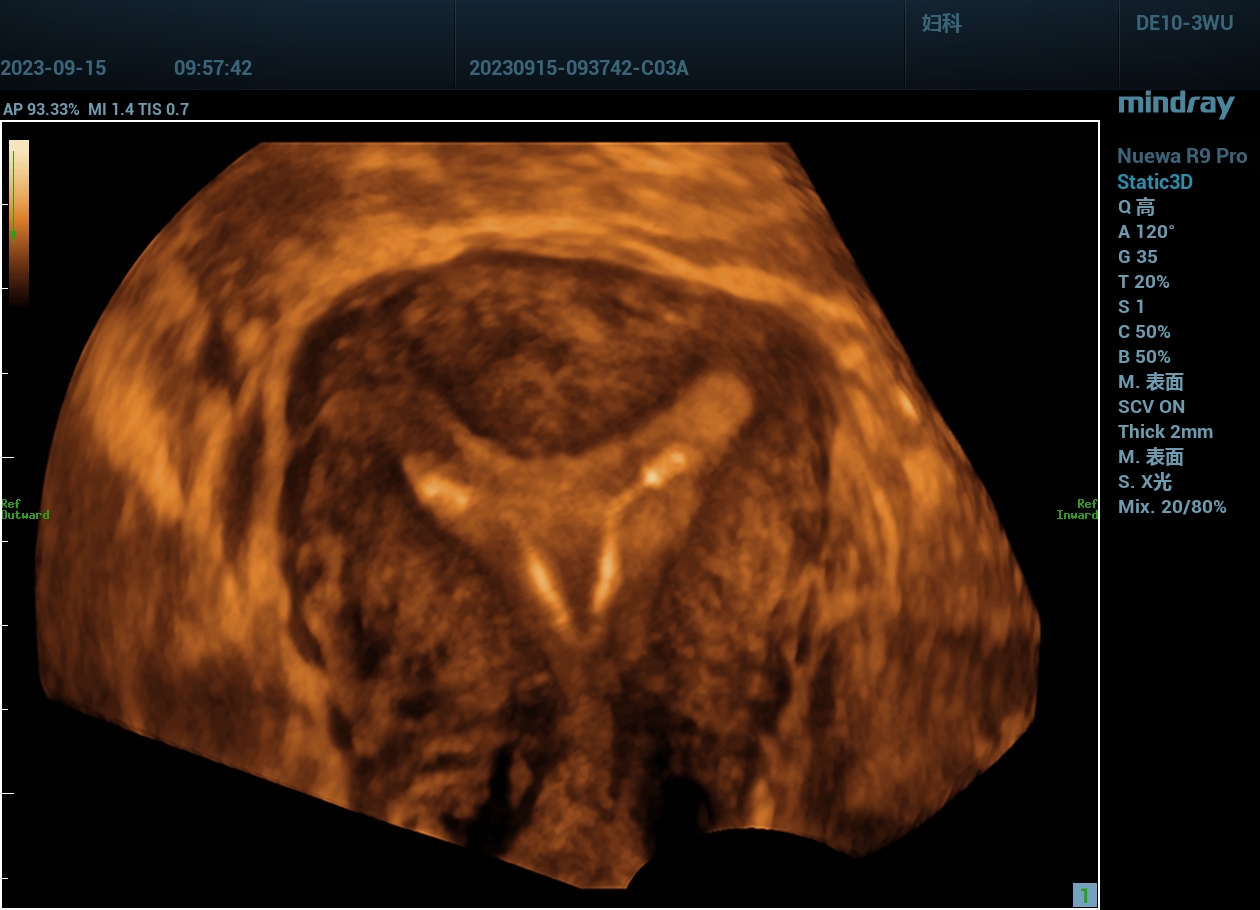

不完全性纵隔子宫声像图:子宫外形正常,但宫底横径较宽;宫底水平横切面显示子宫内部纵隔,其两侧各见一宫内膜回声;三维超声子宫冠状切面成像显示不完全纵隔子宫为Y形。